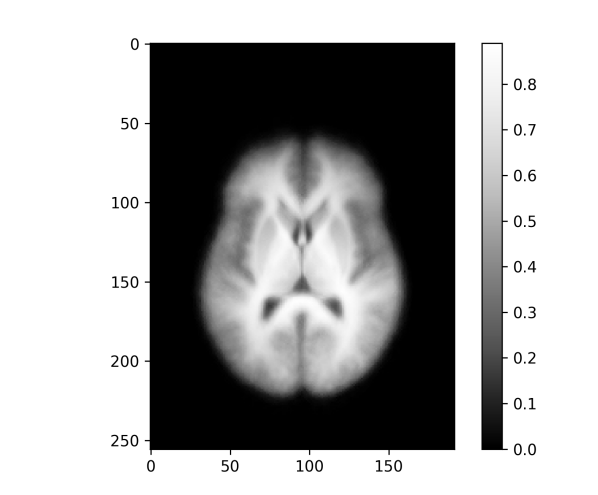

An important application of image registration is the preprocessing of 3d MRI brain images. Here a collection of brain images (possibly from different subjects) are registered with a template, here also called an atlas, which enables more direct comparisons between different brains despite differences in the respective brain geometry before registration. The dataset used here for demonstration purposes is the Neurofeedback Skull-stripped (NFBS) dataset [9], which contains 125 raw MRIs and their skull stripped versions. The intensities of the sample images are normalized such that the median of each image (without the background zeros) is mapped to . Additionally, we are optimizing an intensity scaling factor for each image during the registration such that the scaled template matches the registered image under the similarity metric. This minimizes the vertical variability and brings us a bit closer to the model situation of the shifted edges. The effective height for the resolution measure is chosen as .

For the skull stripped brains a template is generated for affine and rigid transformations and for - and -norm similarity measures, as shown in Figure 10. In each of the four cases the template resolution is computed with Algorithm 1 and horizontal slices of the resulting 3d images of the values are shown in Figure 11 and visualized on top of the template, as described in Subsection III-D, in Figure 12.

Again, the affine registration is more accurate, especially at the boundary of the brain, and the -norm templates appear sharper than the -norm versions but – as revealed by the template resolution measure – are only slightly better in terms of registration accuracy. The rigid registration results are almost identical. In the affine case the -norm leads to better registration at the upper part of the brain (frontal lobe; see Figure 2 for locations), while being similarly inaccurate around the lateral ventricles (twin holes in the lower middle). In all cases the regions in the upper middle of the brain (around the putamen and thalamus) are quite well registered and are also the sharpest regions of the templates across all registration variants. This is in agreement with measurements of the volumes of these brain regions (see e.g. Table 4 in [11] for healthy controls, or Table 2 in [12]) where the coefficients of variation (standard deviation divided by the mean) of the volumes are relatively low for the putamen and thalamus compared with those for the lateral ventricles, the latters’ variability ranging among the highest across all measured regions.